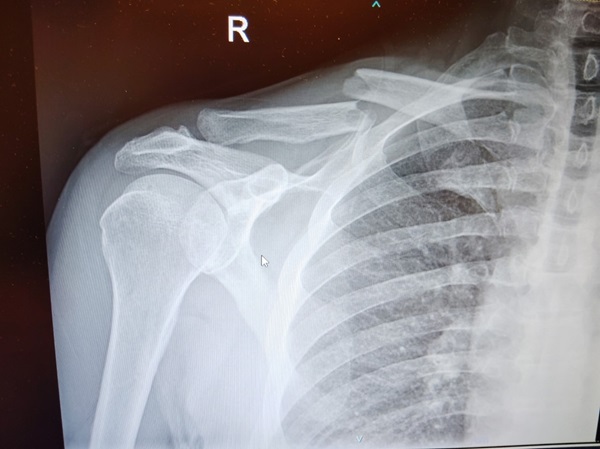

What Is a Broken Clavicle?

Your clavicle, which is commonly referred to as the collarbone, is the long, thin bone that runs between your shoulder blade and breastbone. In a car accident, the force of impact can cause this bone to snap or crack. This can happen during a crash in a variety of different ways, such as:

Symptoms of a broken clavicle may include localized immediate pain, swelling, bruising, and a grinding or popping sound at the time of impact. Some people may also notice their shoulder visibly drooping, or the fractured bone may raise and “tent” the surrounding skin, or they may feel sharp pain when trying to raise their arm.

Treatment for a broken collarbone typically depends on the severity and location of the break. For simple fractures, doctors may recommend immobilization using a sling or brace, followed by physical therapy. But more complicated fractures—especially those involving multiple breaks or displacement—may require surgery and long-term rehabilitation.